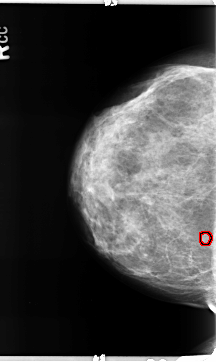

ics_version 1.0 filename B-3157-1 DATE_OF_STUDY 9 6 1997 PATIENT_AGE 42 FILM FILM_TYPE REGULAR DENSITY 2 DATE_DIGITIZED 5 5 1998 DIGITIZER LUMISYS LASER SEQUENCE LEFT_CC LINES 4720 PIXELS_PER_LINE 2928 BITS_PER_PIXEL 12 RESOLUTION 50 NON_OVERLAY LEFT_MLO LINES 4736 PIXELS_PER_LINE 2704 BITS_PER_PIXEL 12 RESOLUTION 50 NON_OVERLAY RIGHT_CC LINES 4704 PIXELS_PER_LINE 2800 BITS_PER_PIXEL 12 RESOLUTION 50 OVERLAY RIGHT_MLO LINES 4672 PIXELS_PER_LINE 3032 BITS_PER_PIXEL 12 RESOLUTION 50 OVERLAY |

FILE: B_3157_1.RIGHT_CC.OVERLAY TOTAL_ABNORMALITIES 1 ABNORMALITY 1 LESION_TYPE MASS SHAPE LOBULATED MARGINS CIRCUMSCRIBED ASSESSMENT 4 SUBTLETY 4 PATHOLOGY BENIGN TOTAL_OUTLINES 1 BOUNDARY |